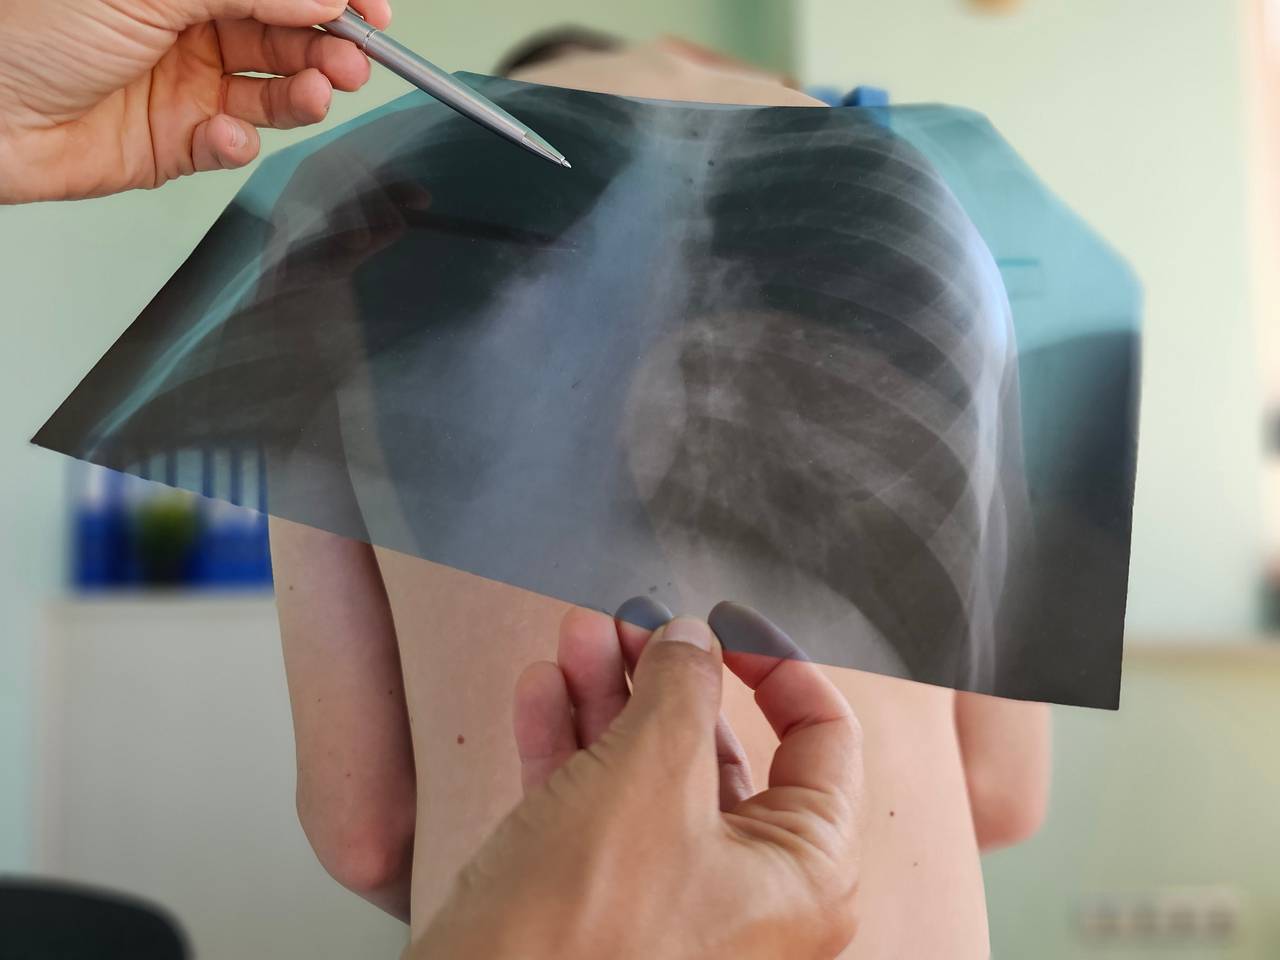

В Новосибирске в одной из школ были введены ограничения после того, как среди учащихся были обнаружены случаи туберкулеза. Об этом сообщили в мэрии города.

Специалисты Роспотребнадзора сейчас занимаются установлением источника и причин заболевания. Учителя и ученики, которые контактировали с заболевшими, прошли внеплановую диагностику. В мэрии не уточнили количество заболевших детей, ссылаясь на врачебную тайну.